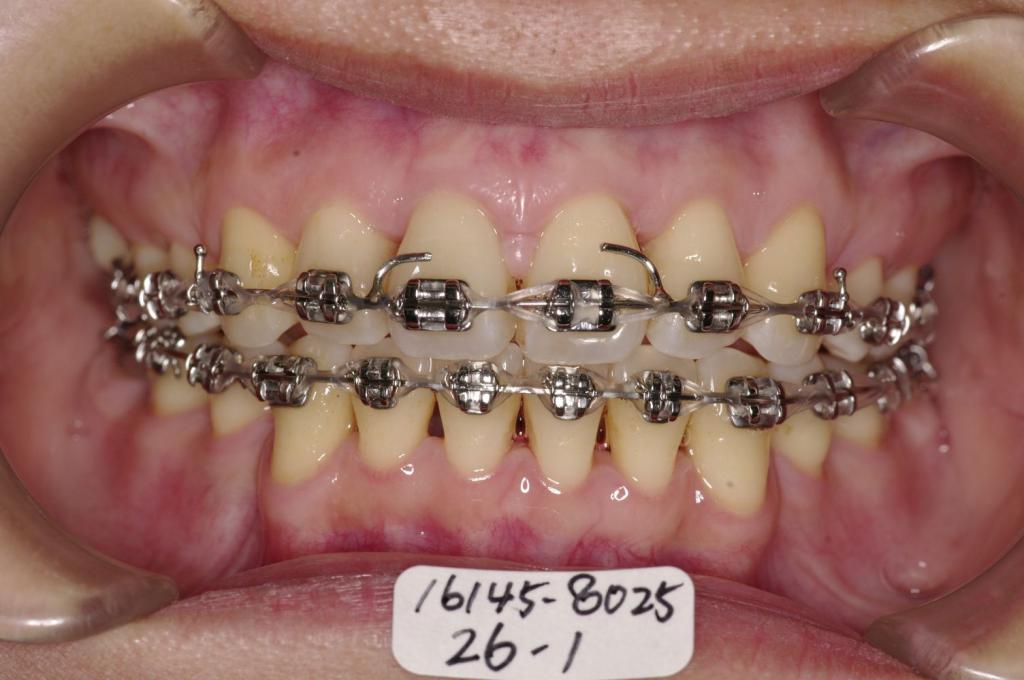

装置の種類及び治療法 診断:上下顎前突

治療方法および装置:マルチブラケット装置

High pull J-hook headgear

抜歯:右上4 /左上4

右下84 /左下48

装置写真

治療前

前歯、出っ歯・開咬の矯正治療前口内写真NO.1101